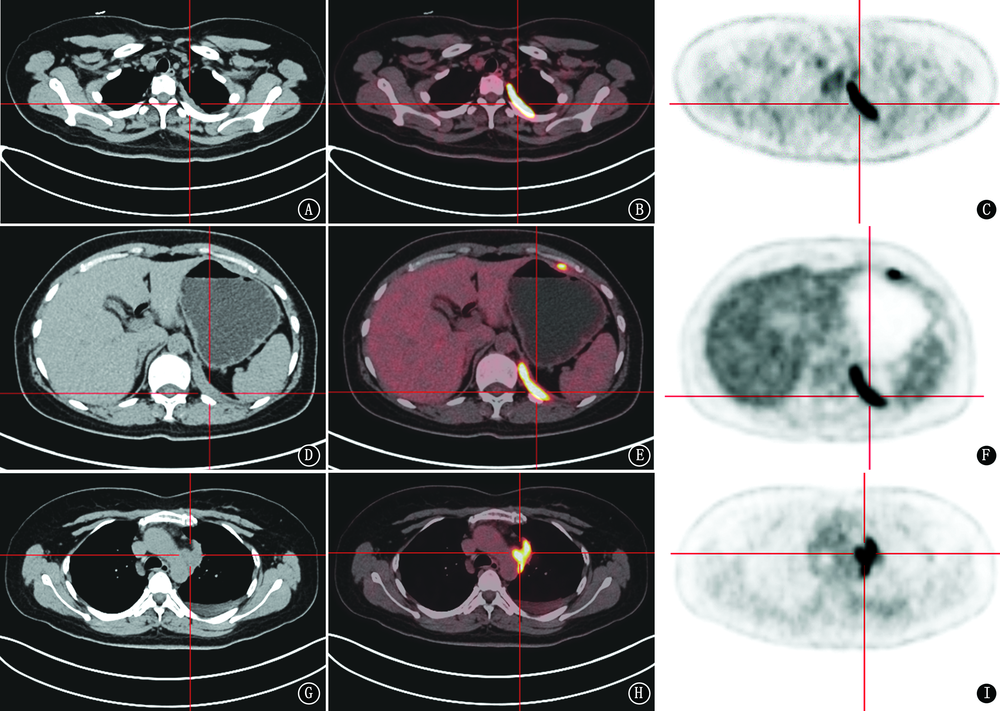

宫颈癌的主要转移途径是直接蔓延、淋巴转移和血行转移,较常见的远处转移部位为肺、肝、骨骼等,宫颈癌胸膜转移报道较少,现报道1例宫颈癌发生胸膜转移并快速进展导致死亡的病例,以提高对少见部位转移的宫颈癌的重视。